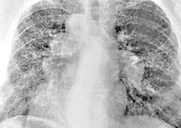

◈ 베릴륨 독성 문제

베릴륨은 독성이 매우 강하다. 특히 미세한 베릴륨 입자를 흡입할 경우 폐에 심각한 염증을 일으키는 베릴리움증(Berylliosis)이라는 질환이 발생할 수 있어, 산업 현장에서는 철저한 안전 관리와 엄격한 보호장비 및 환기 시스템이 필수다.